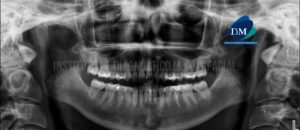

Paciente pediátrico de sexo masculino acude al Instituto de Diagnóstico Maxilofacial para evaluación imagenológica. En la radiografía panorámica observamos las estructuras óseas de características conservadas,